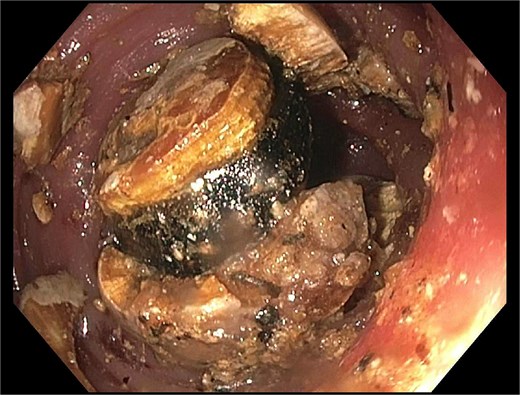

A subsequent attempt with a dual-channel colonoscope allowed for mechanical lithotripsy via trapezoid basket, successfully fragmenting the stone (Figs 4–6). The patient resumed a regular diet, passed flatus and stool, and was discharged with outpatient follow-up for elective cholecystectomy.